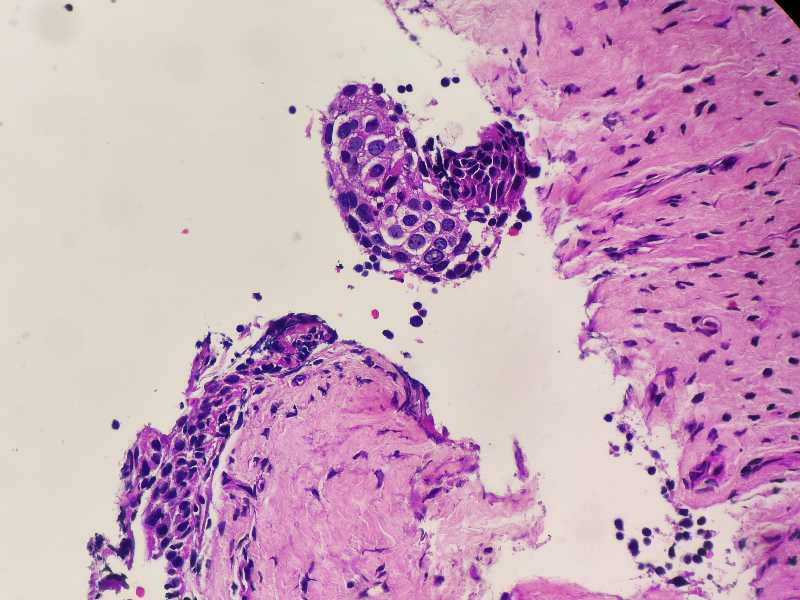

女59岁宫颈活检HPV58+